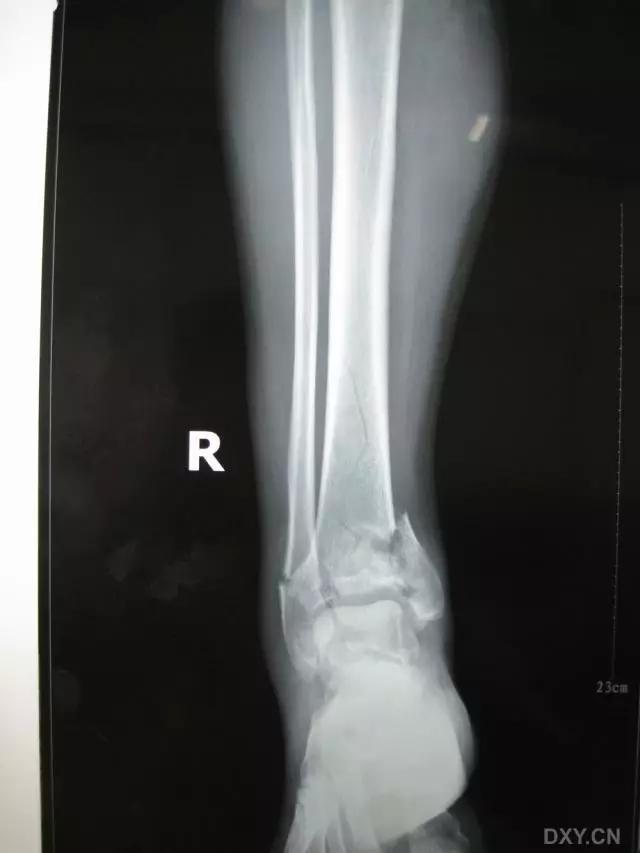

5. Maisonneuve 骨折

腓骨近端骨折伴内踝骨折及三角韧带断裂。

(来源:Radiopaedia)